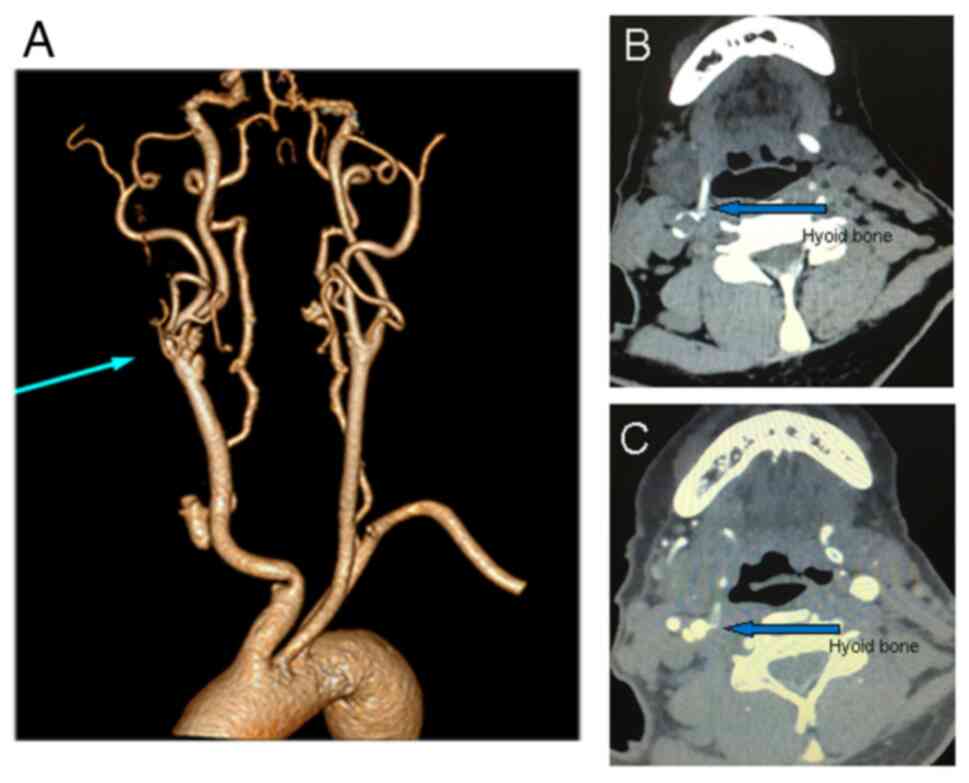

Contrast-enhanced computed tomography revealed two cysts with some calcification located at the bifurcation of the right internal carotid artery (ICA) and the right greater horn of the hyoid bone adjacent to the right ICA (Fig. 2).

Figure 2

Contrast-enhanced computed tomography revealed two cysts with some calcification. (A) CTA with 3D reconstruction revealed two cysts with some calcification located at the bifurcation of the right ICA and stenosis of the origin of the right ICA. Computed tomography (B) without or (C) with contrast material revealed the greater horn of the right side of the hyoid bone adjacent to the right ICA. CTA, computed tomography angiography; ICA, internal carotid artery.